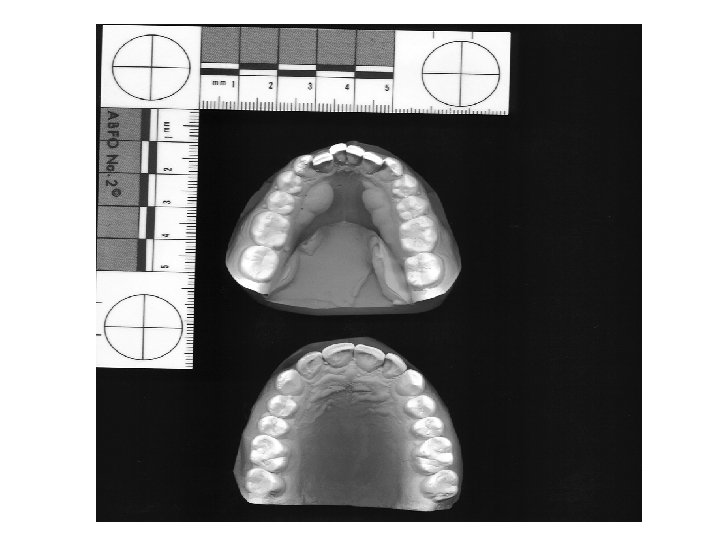

BITE MARK ANALYSIS • • Scaled photography of bite mark evidence Scaled photography of dental casts Clinical comparisons Computer comparisons

Teeth Impressions • Connect suspect to bite mark: